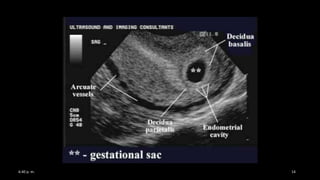

• SIGNO DOBLE DECIDUAL

– Diferenciación entre embarazo

intrauterino precoz y reacción decidual

secundaria a embarazo ectópico

– Dos anillos ecogénicos en la cavidad

endometrial

• Decidua parietalis : anillo externo, capa

decidual del útero

• Decidua capsularis: anillo interno, cubre el

margen libre del saco gestacional.

• Decidua basal: base endometrial del saco. +

corion frondoso : placenta.

Ecografía normal

Signo de la Doble Decidua

Sin embargo el ver el signo no es diagnostico de

embarazo viable

Importante ver la doble decidua para no pasar un saco ectópico